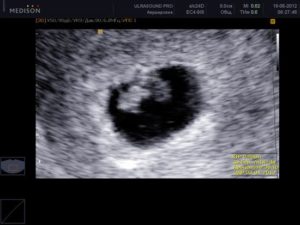

Когда УЗИ определяет наличие эмбриона в плодном яйце и как он выглядит?

Если зачатие произошло у женщины с регулярным менструальным циклом, диагност обнаружит эмбрион на 6–7 неделе. К этому времени размер плодного яйца увеличивается до 7 мм.

Кроме того, в ходе УЗИ прослушивается сердцебиение зародыша. На мониторе эмбрион выглядит как буква «С». Ближе к концу 8-й недели беременности появляются хорошо различимые очертания головы, ножек и ручек.

Со следующей недели зародыш уже считается плодом.